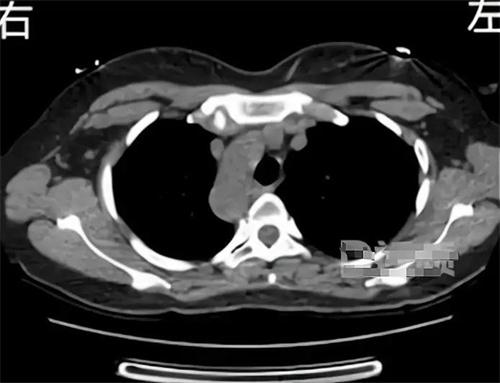

近期,來自陜西寶雞的一名女子在就醫(yī)時(shí),發(fā)現(xiàn)自己是十分罕見的“鏡面人”,因?yàn)槲迮K六腑全部都長反了。醫(yī)生在檢查這位女子身體情況時(shí),發(fā)現(xiàn)膽囊、脾臟、肝臟、內(nèi)臟等,器官與常人完全相反,在醫(yī)學(xué)領(lǐng)域中被稱為“鏡面人”。“鏡面人”是一種特別罕見的生理現(xiàn)象,發(fā)現(xiàn)概率是百萬分之1,盡管這種病例在全球范圍都是比較罕見的,但是“鏡面人”生理功能與正常人來講沒有很大的區(qū)別,在生活與工作中都不會(huì)有太大的影響。

“鏡面人”并不是第1次出現(xiàn)在醫(yī)學(xué)文獻(xiàn)中,20世紀(jì)70年代就有學(xué)者報(bào)道過類似的病情,在這類病例中,患者不僅內(nèi)部器官位置與常人相反,也有一系列的醫(yī)學(xué)特征,比如心臟大小和形態(tài)出現(xiàn)異常,當(dāng)然這種病例發(fā)生幾率比較低,所以很少有人會(huì)遇到這樣的情況。對(duì)于這類情況的成因醫(yī)學(xué)領(lǐng)域沒有明確的結(jié)論,有學(xué)者分析,有可能是與胚胎發(fā)育中基因突變有關(guān),也有一部分學(xué)者認(rèn)為,這種病例有可能是一種遺傳疾病,但是不具備傳染性和遺傳性。